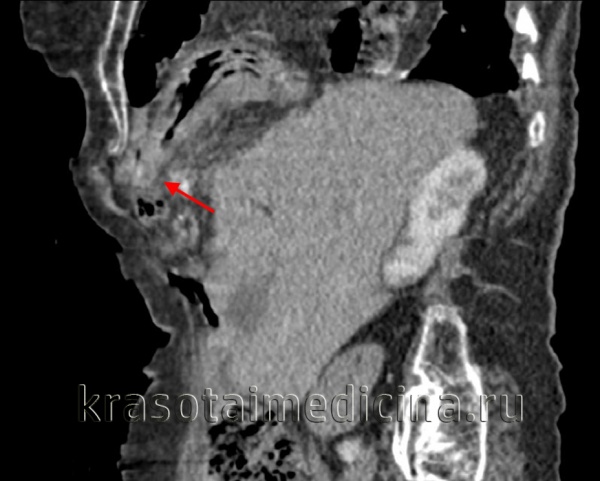

(Слева) На аксиальной КТ с контрастным усилением определяется глубокий разрыв селезенки и активная экстравазация. Обратите внимание на разрыв нижнего полюса селезенки, где обнаруживается участок высокой плотности, свидетельствующий об артериальной экстравазации.

(Справа) На аксиальной КТ с контрастом у этой же пациентки определяется большая гематома около селезенки, а также признаки интенсивной артериальной экстравазации.